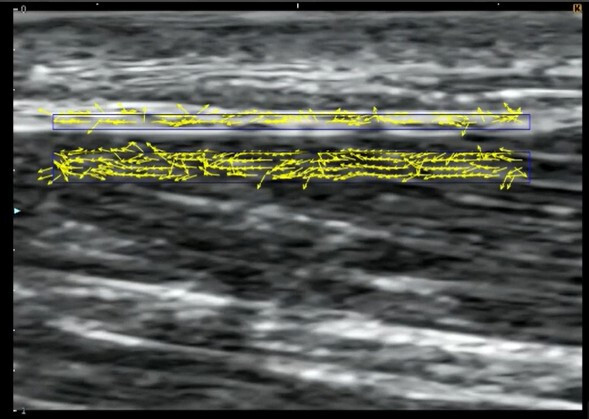

Ultrasound video data were analyzed using specialized software (Echolizer, GLAB Inc., Hiroshima, Japan), which calculates optical flow using the Farneback method (frame offset: 3).20 The validity and reliability of this software for quantifying tissue motion have been confirmed in previous studies, with a relative error of 0.2% after applying the embedded regression equation.21 Regions of interest (ROIs) were defined using a standardized grid system as follows:

Superficial ROI: fascial tissue (X: 12.45 mm × Y: 0.38 mm)

Deep ROI: medial gastrocnemius muscle (X: 12.45 mm × Y: 0.75 mm) (Figure 4)

The mean displacement velocity along the X-axis (cranial–caudal direction) was calculated for each ROI. Cross-correlation analysis was then performed between the fascial and muscular velocity profiles, and the mean value from three trials was used for statistical analysis. A higher cross-correlation coefficient indicated more synchronized movement between the two tissues, representing reduced gliding, whereas a lower coefficient indicated more independent movement, representing increased gliding. This interpretation was based on previous research investigating gliding between the vastus lateralis and subcutaneous tissue.22